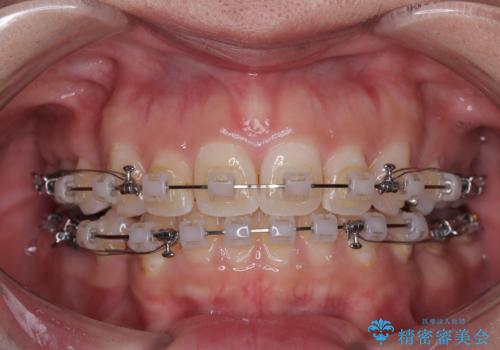

- 矯正装置

- クリアブラケット

- 口元の突出感と奥歯のむし歯を気にして来院された患者様です。

奥歯の虫歯は事前に矯正治療用の仮歯に置き換えて矯正治療を行い、装置除去後にセラミッククラウンにて補綴治療を行うこととしました。

通常は上下左右の第一小臼歯4本を抜歯することになりますが、左側下顎の第二小臼歯は既に根管治療をされており、予後が良くないとのことでこの歯を抜歯し、ワイヤー装置にて矯正治療を行うこととしました。